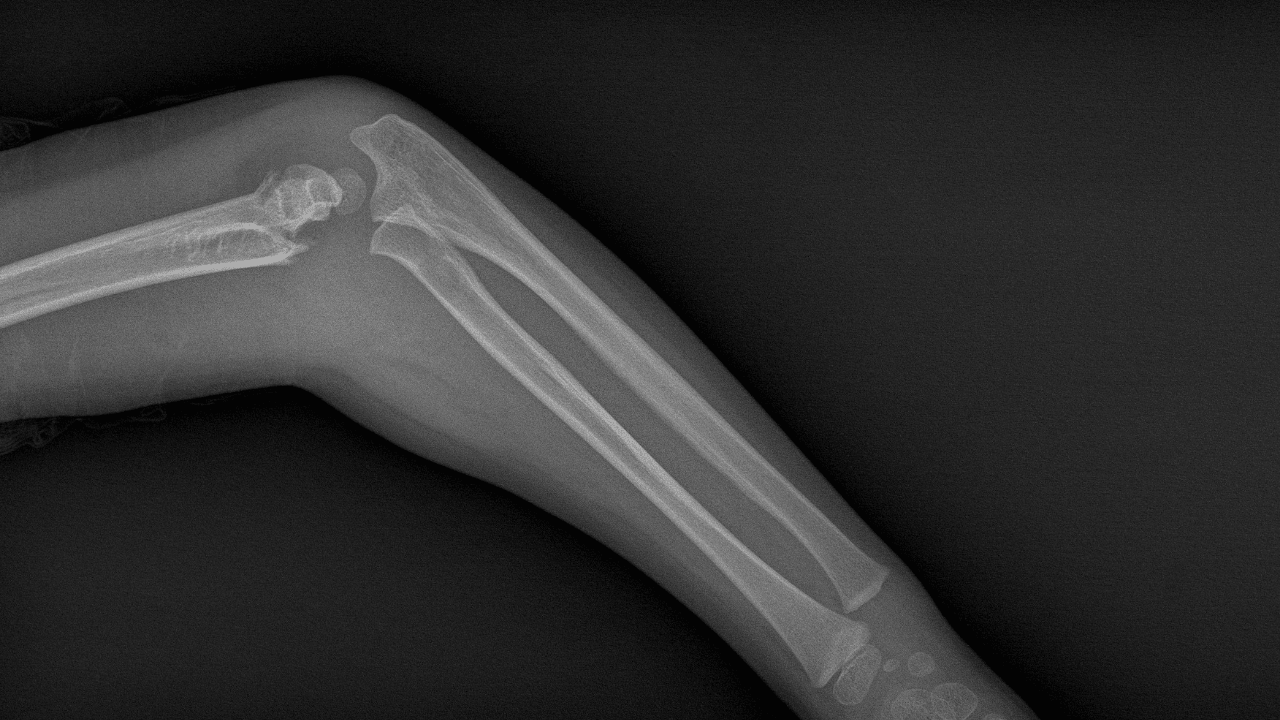

Parçalı (komminüte) kırıklarda çok sayıda minik kemik parçasını anatomik olarak hizalayıp sabitlemek zor; klasik metal implantlar bu mikrof ragmentleri zahmetli ve kimi zaman yetersiz biçimde tutar. Hızlı yapışan, ıslak-kanlı ortamda çalışan, sonradan vücutta eriyen bir yapıştırıcı; operasyon süresini ve ikincil çıkarma ameliyatlarını azaltma, enfeksiyon ve yumuşak doku hasarı riskini düşürme potansiyeli taşır.